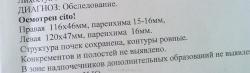

Уважаемые коллеги! На представленный урограммах имеется гидронефротическая трансформация правой почки и правого мочеточника, вероятнее всего из за наличия рентгенонеконтрастного камня расположенного в правом мочеточнике над входом в малый таз. Незначительное нарушение выделительной функции правой почки. Конечно же, большой вопрос к докторам УЗД. Не видить такое расширение полостной системы почки - лучше прекратить заниматься ультразвуковой диагностикой. В защиту коллег, возможно УЗИ проводилось сразу после приступа МКБ или на его высоте, тогда расширения полостной системы можно и не наблюдать!

Владимир Васильевич, камень ниже, чем над входом в малый таз...он всего на пару см выше устья....как мне кажется. Вопрос к автору - временной промежуток между УЗИ и в\в урографией - в часах или сутках?

За двое суток эта самая пиелокаликоэктазия и могла развиться...пока нет причины "наезжать" на УЗИстов.

Поддерживаю пост Виктора Григорьевича, к врачу УЗИ не может быть ни каких претензий! Прошло 2 суток после приступа. ИМХО: правый мочеточник несолько расширен, но говорть о расширении собирательной системы правой почки неправомочно( тем более, о гидронефротической трансформации последней).